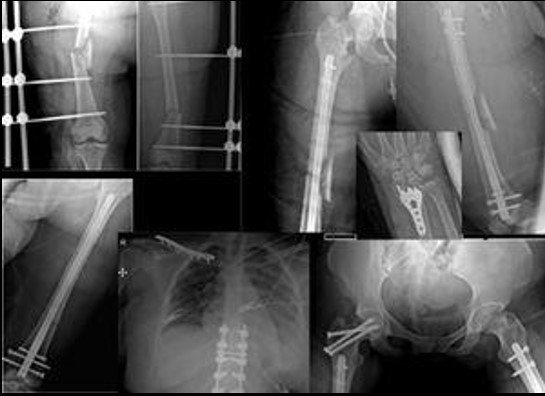

The definitive stabilization of long bone fractures in the first 24 hours positively impacts survival1,21-23. Hemodynamically stable patients should undergo definitive fixation of fractures during the first surgery (Figura 3). However, prolonged interventions (over 90 minutes) in hemodynamically unstable patients are associated with unfavorable outcomes. Furthermore, major surgery can trigger and increase immune response resulting in a clinical condition called “Second Trauma” 15,17,24. Therefore, delayed definitive stabilization has been implemented in hemodynamically unstable patients to reduce the effect of the second trauma 25,26. These patients should undergo damage control with a temporary fixation, followed by physiologic stabilization and a deferred definitive fixation in a second surgical time 5 to 10 days after damage control (Figura 4) 10,16,27,28.